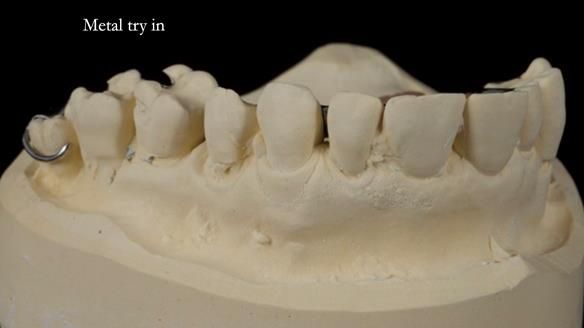

Welcome to Newsletter 64. I'll walk you through the process of providing a Mk 2 metal-based partial denture (RPD), for Ian a retired Veterinary Surgeon aged 78. The RPD was made at an increased vertical dimension and acted as an occlusal stabilisation splint - reducing the wear and bite force on the remaining natural teeth.